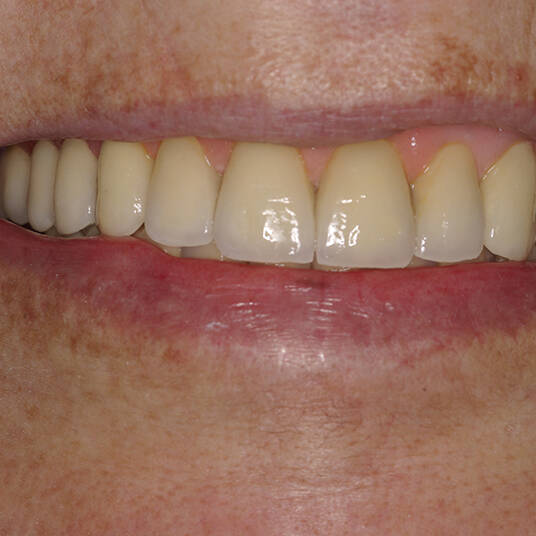

Na Clínica Pontes Odontologia, somos referência em implantes dentários em Fortaleza, oferecendo tratamentos de alta qualidade e tecnologia de ponta. Os implantes dentários são estruturas de titânio posicionadas cirurgicamente no osso maxilar ou mandibular para substituir as raízes dos dentes ausentes. Essa técnica permite a fixação de próteses personalizadas, restaurando a função mastigatória, a estética e a autoestima dos nossos pacientes.

Nosso compromisso é oferecer um tratamento de excelência, com profissionais especializados e tecnologia de última geração para implantes dentários em Fortaleza. Venha nos visitar e descubra por que a Clínica Pontes Odontologia é referência em implantes dentários em Fortaleza, devolvendo sorrisos e qualidade de vida aos nossos pacientes.